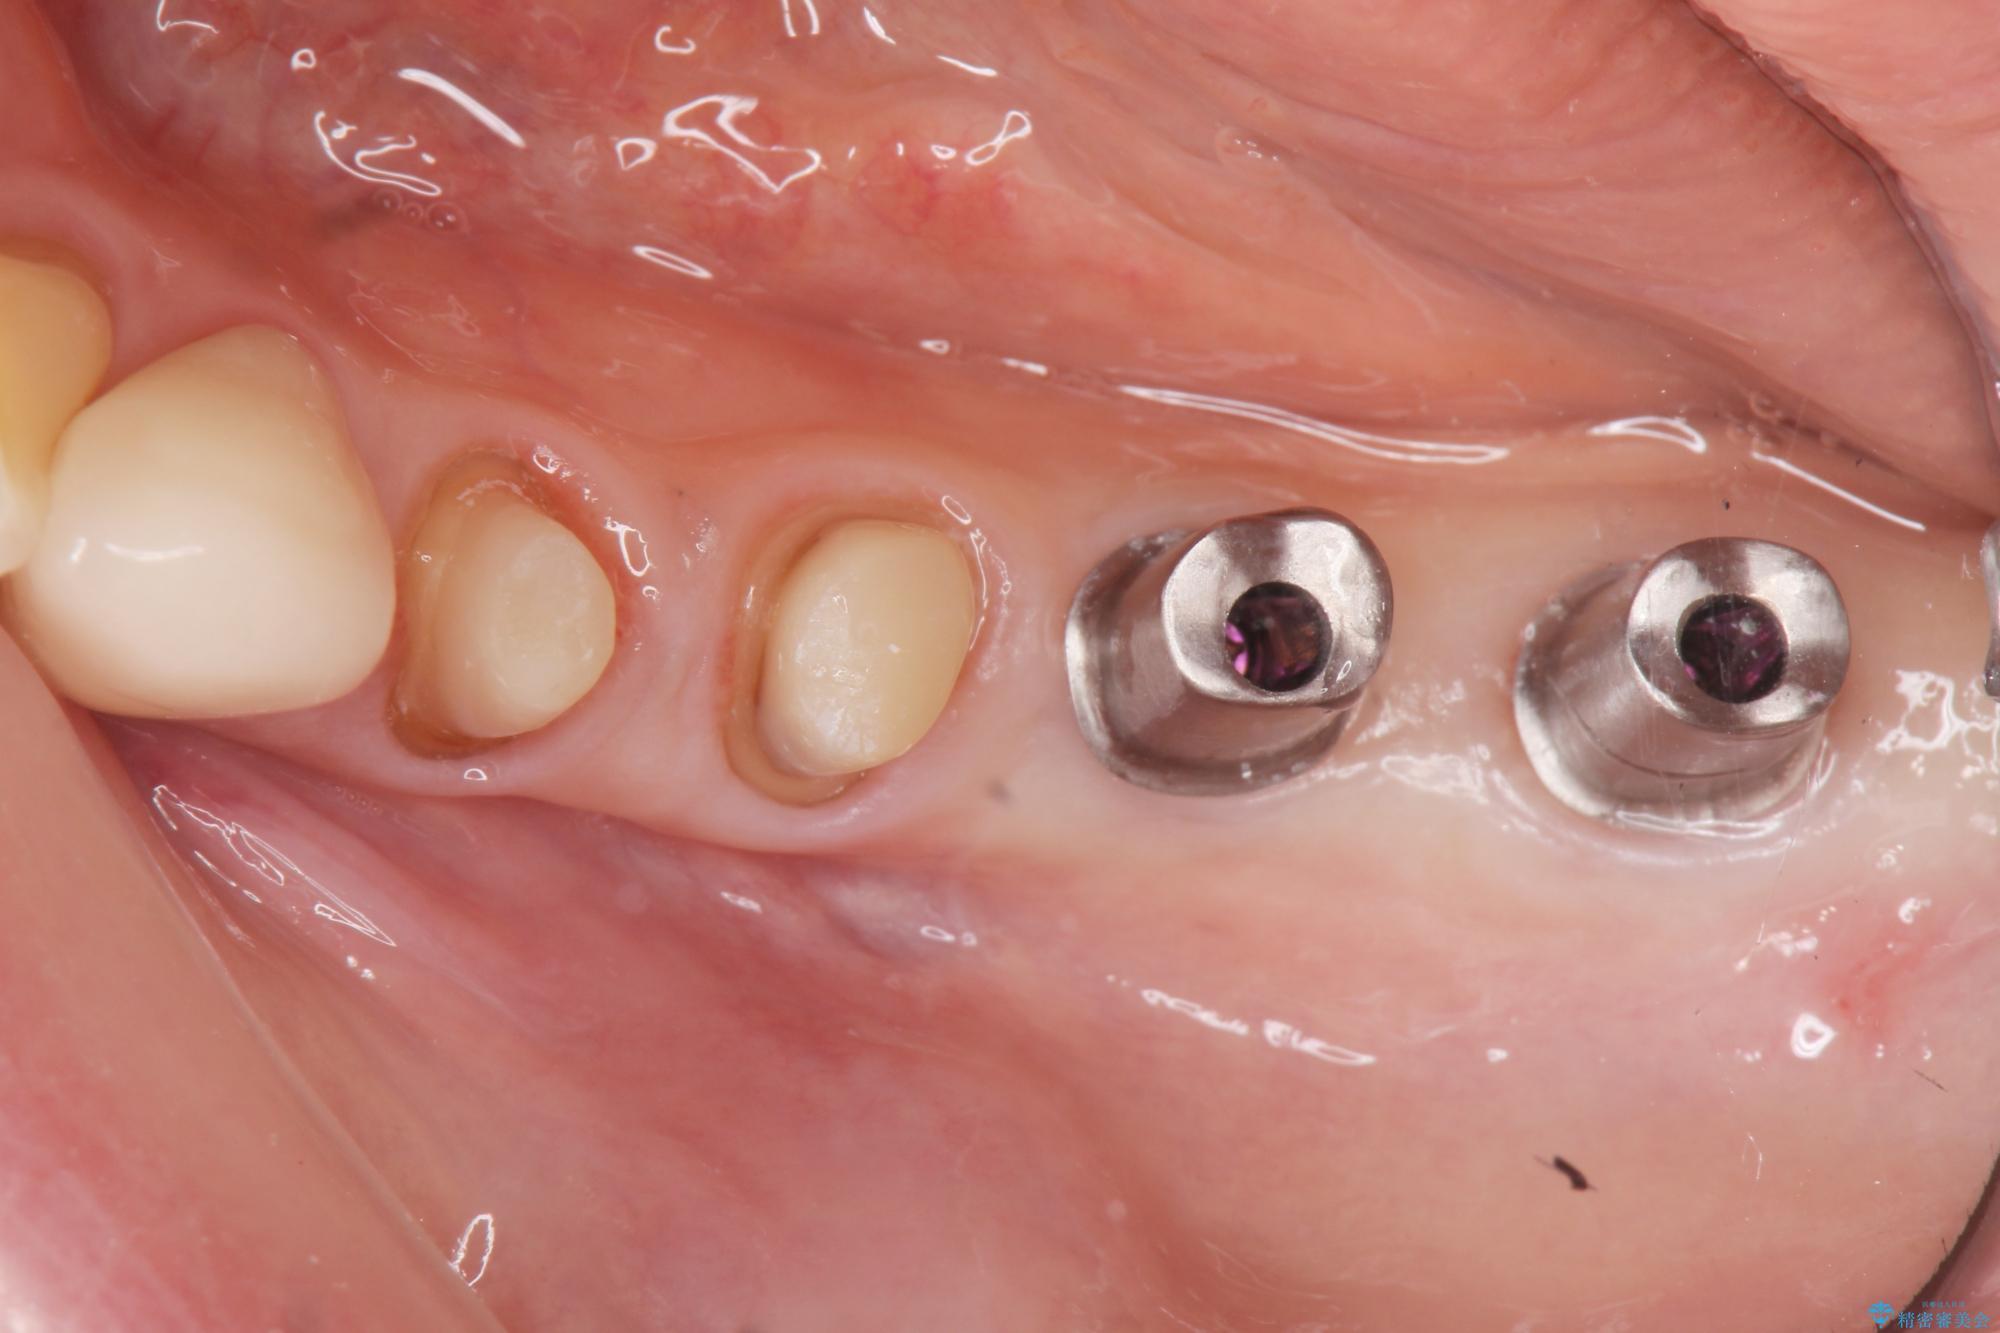

治療中

劣化の進んだブリッジの再治療[ 不適合な補綴物による虫歯の再発 ] 治療中画像 劣化の進んだブリッジの再治療[ 不適合な補綴物による虫歯の再発 ] 治療中画像 劣化の進んだブリッジの再治療[ 不適合な補綴物による虫歯の再発 ] 治療中画像